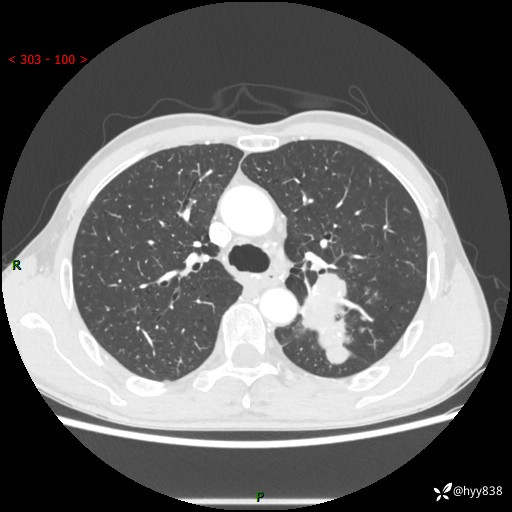

现病史:患者余4月前发现咳嗽咳痰伴痰中带血,无胸闷、胸痛、头晕、恶心、呕吐等不适,2天前因体检发现肺部结节遂于当地市第一人民医院行胸部CT薄层平扫+三维重建示:1.左肺上叶尖后段占位性病变考虑肿瘤性病变伴阻塞性肺炎,右肺上叶后段磨玻璃结节。2.肝内多发囊性灶、左肾结石。现患者为求进一步治疗,于我院门诊就诊,门诊以“肺结节”收入院。 自患病以来,精神、饮食、睡眠尚可,大小便正常,体力体重无明显减轻。

胸部CT增强扫描(外院平扫)